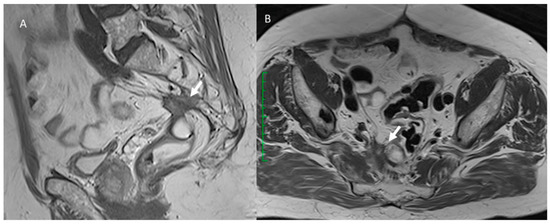

3.7. Local Recurrence